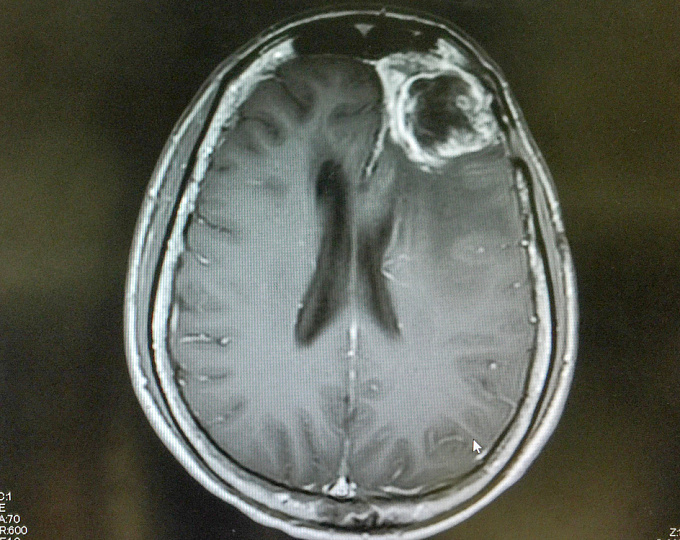

Прогноз пациентов с первичной глиобастомой спинного мозга

Первичная глиобластома спинного мозга – крайне редкая опухоль, которая чаще всего характеризуется очень неблагоприятным прогнозом. Однако из-за ее невысокой частоты встречаемости точные статистические данные о выживаемости пациентов недоступны.

В связи с чем целью данного исследования было изучение течения глиобластомы спинного мозга.